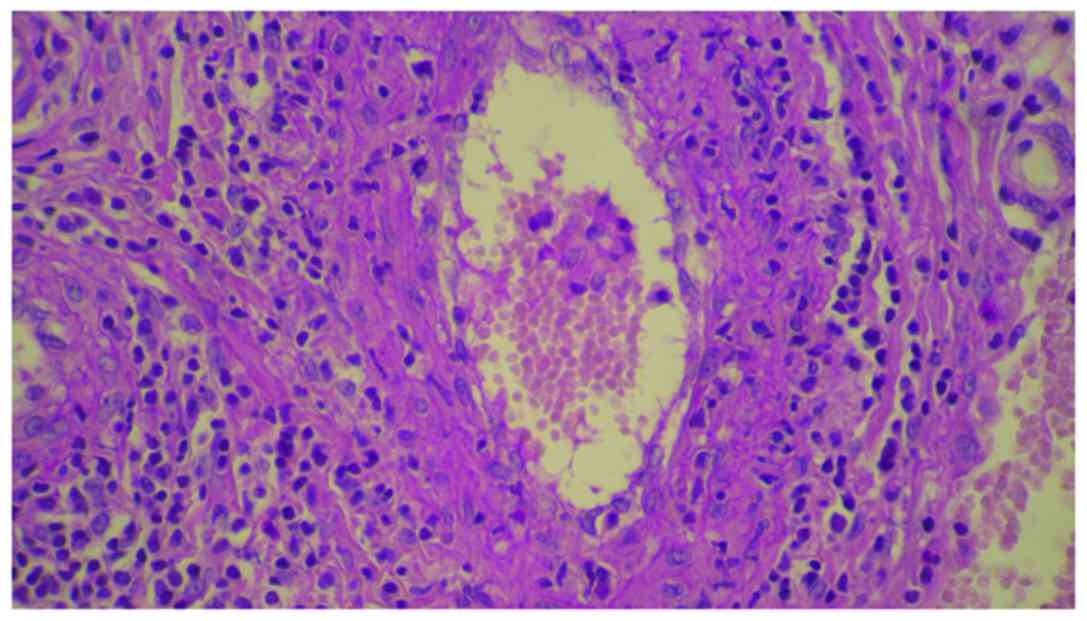

erlotinib, but unfortunately, it was not possible. Skin biopsy was

performed. The histopathology revealed a dense perivascular

neutrophilic infiltration, fibrinoid necrosis of the vessel walls,

leukocytoclastic and red blood cell extravasation, confirming the

diagnosis of cutaneous leukocytoclastic vasculitis (Figs. 3 and 4). The appearance of cutaneous vasculitis